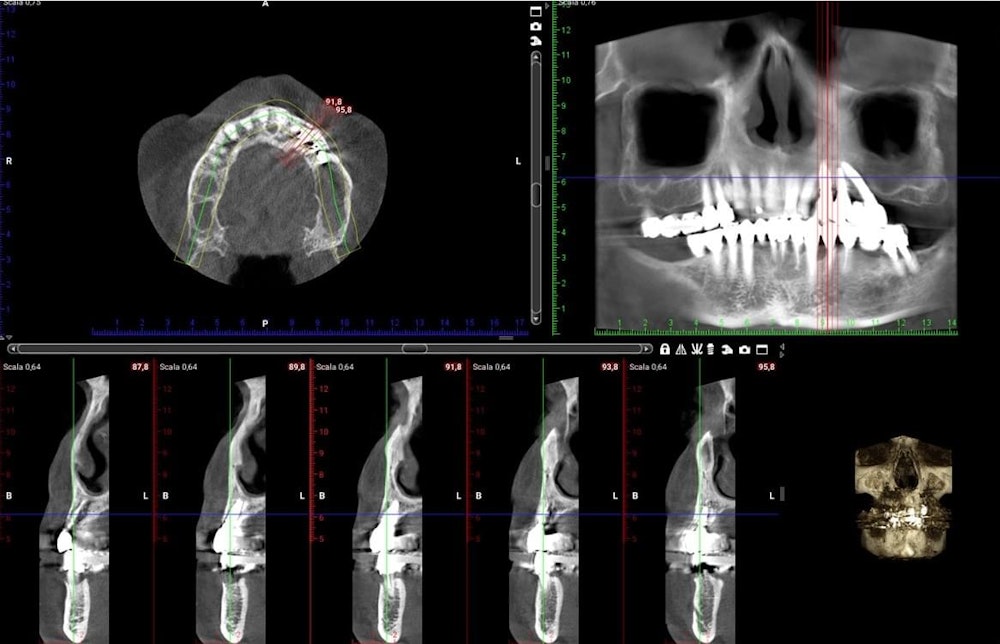

Digital implant project: three different views of the same procedures.

X-ray and CBCT post-op.